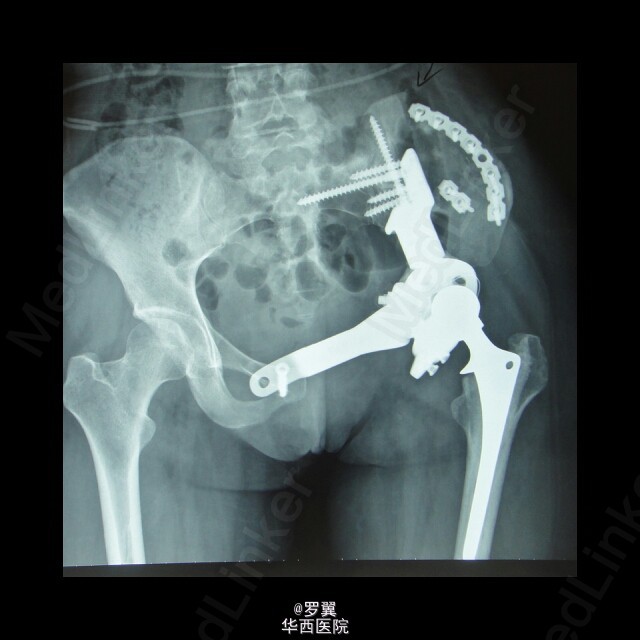

骨盆恶性肿瘤半骨盆假体置换术后髂骨断裂

患者23岁女性,骨盆恶性肿瘤半骨盆假体置换术后,进行髂骨保留并予钢板螺钉内固定,术后2年残留髂骨疲劳断裂。。